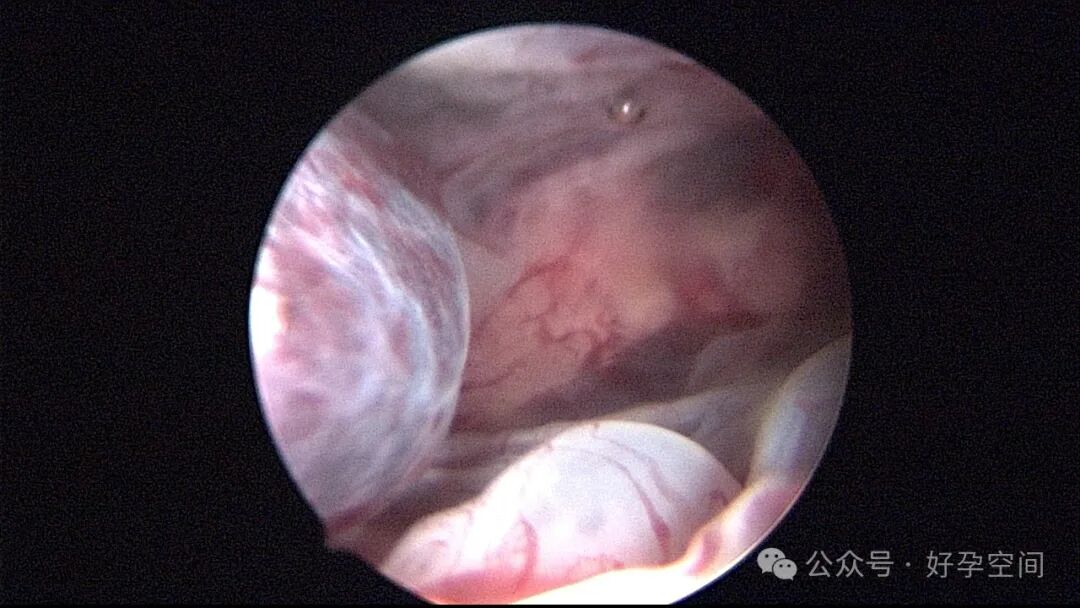

患者24岁,G6P3,顺产1次,双胎剖宫产1次。本次停经53天,计划外妊娠,行宫腔镜取胚及安环术。摘除胚胎后见宫腔右侧壁胚胎附着部位包块,约1.0cm*1.0cm*0.8cm,宫腔镜切除包块送病检,放置γ环一个,环两臂卷曲于右侧宫角,宫腔镜钩住环尾部下拉,上推节育环右臂,将环调整到正常位置。术后病检结果为“宫腔胎盘附着部位超常反应”。